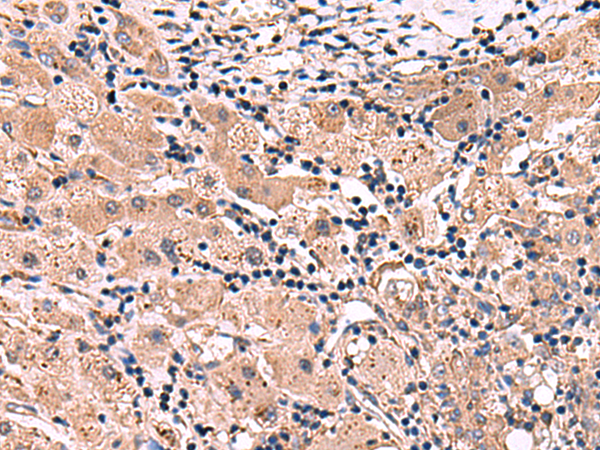

IHC positive control: |

Human tonsil and Human liver cancer |

IHC Recommend dilution: |

50-300 |